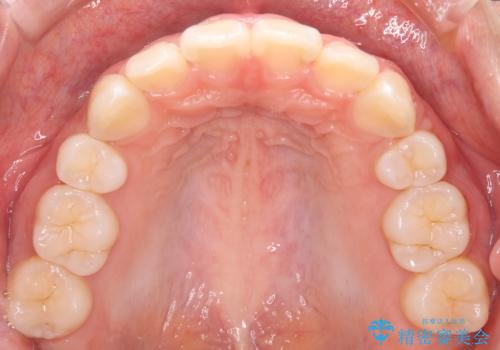

抜歯矯正をして口元を下げたことで、口元が下がりEラインが大変綺麗になりました。

矯正期間も1年9ヶ月と比較的短期間で終了することができました。